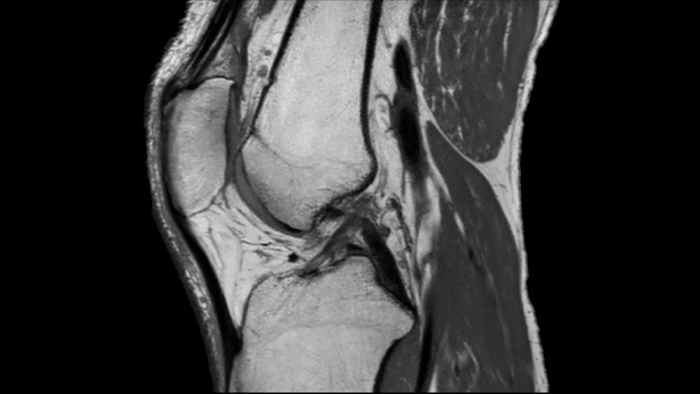

3D MSK View

Clinical application

MSK

Q-Scan Group, Australia